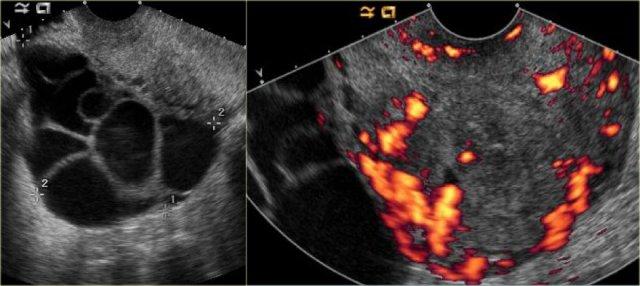

Trên siêu âm, cả hai buồng trứng đều to rõ rệt và chứa các thành phần nang với các thành phần đặc trong lòng nang (mũi tên).

Các tổn thương đặc-nang phức tạp, kết hợp với tính chất hai bên, rất nghi ngờ cho u nang buồng trứng thực sự và cần được đánh giá thêm.

Một lần nữa, vai trò của chẩn đoán hình ảnh là xác nhận sự hiện diện của tổn thương và kết luận rằng đây không phải là tổn thương có thể được phân loại chắc chắn là lành tính, cũng không phải là tổn thương có thể theo dõi an toàn: cần phải có hành động can thiệp.

CT của cùng bệnh nhân xác nhận các tổn thương đặc-nang phức tạp hai bên kích thước lớn, phồng vào ổ bụng.

Mục đích của CT không phải là xác nhận những gì đã biết từ siêu âm, mà là để phân giai đoạn bệnh.